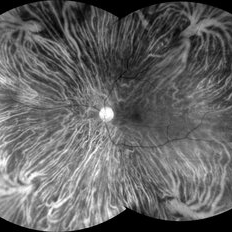

Red LED (585 - 640nm) confocal scanning laser ophthalmoscopy of a 37-year-old male with myopia highlighting choroidal vessels and vortex veins.

Photographer: Juliana Rio, MD. Leitão Guerra - Oftlamologia, Salvador - Brazil

Imaging device: Zeiss Clarus 7000

Condition/keywords: myopia, retina, tigroid Fundus, vortex vein